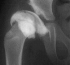

At 5 + 8 years of age

,

a clinical diagnosis of Charcot-Marie-Tooth disease was made, and Shelf

arthroplasty was performed to increase the femoral head coverage.

On the last evaluation (10 years old), the patient was pain free, and showed

acceptable range of motion, however, his right limb is 3 cms. short and

the patient is wearing a 2 cm. shoe lift.